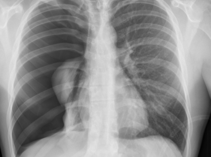

Die häufigsten Fragestellungen betreffen das Knochenskelett und die Lunge (Thorax). Die Aufnahmen des Thorax dienen z.B. zum Ausschluss akuter und chronisch entzündlicher Lungenveränderungen, zum Ausschluss von Tumoren im Bereich des Brustkorbs bzw. der Lunge und zur Beurteilung der Herz-Kreislauf-Situation.

Beispielbilder